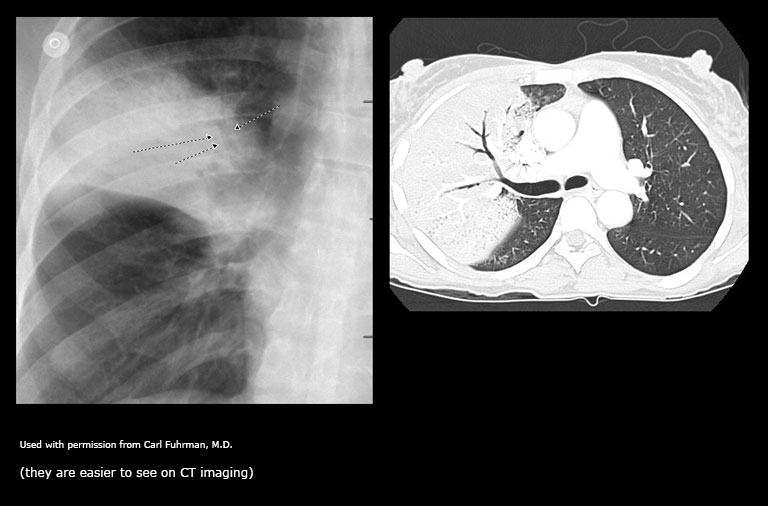

Radiographic Findings in Pulmonary Embolism (PE)

Due to its relative lack of sensitivity, the chest x-ray in patients with suspected pulmonary embolism is usually relegated to the role of ruling out other disorders which may have a similar clinical presentation. The chest x-ray is also very useful when interpreting ventilation-perfusion scans. Though the majority of patients with pulmonary embolism in retrospect do have abnormalities on the chest x-ray, findings are usually too non-specific to be of diagnostic value. Without infarction there are few chest film signs of pulmonary emboli. These include discoid atelectasis, elevation of the hemidiaphragm, enlargement of the main pulmonary artery into what has been described as the shape of a “sausage” or a “knuckle” (Palla’s sign), and pulmonary oligemia beyond the point of occlusion (Westermark’s sign). Occasionally, pulmonary embolisms will cause infarction causing a unique constellation of radiographic signs. Multifocal consolidation of the affected lung may occur in 12 to 24 hours following the embolic event. A consolidation which begins at the pleural surface and is rounded centrally is called a Hamptom’s Hump. These types of consolidation differ from pneumonia in that they lack air bronchograms. Up to 50% of patients with pulmonary embolism will also have ipsilateral or bilateral pulmonary effusions, although these are certainly nonspecific findings. Nevertheless, it is unusual for pulmonary infarctions to be diagnosed by chest radiography although infarctions are known to occur much more frequently. Presumably infarcts are confused with or indistinguishable from atelectasis or pneumonia. Despite the low sensitivity of these signs, the chest radiograph remains an important first step in the diagnosis of pulmonary embolism, primarily to exclude other causes of hypoxemia and to aid in the interpretation of the ventilation/perfusion scan.

May see: Westermark’s sign (oligemia in area of involvement), increased size of a hilum (caused by thrombus impaction), atelectasis with elevation of hemidiaphragm and linear or disk shaped densities, pleural effusion, consolidation, and Hampton’s hump (rounded opacity). In the case of pulmonary infarctions, the main radiographic feature is multifocal consolidation at the pleural base in the lower lungs.